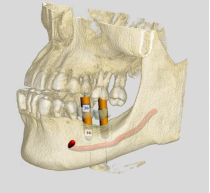

(锥形束CBCT为重建三围模型提供精准数据、计算机辅助设计软件辅助医生定制精准方案)

数字化种植牙就是指利用数字化技术辅助医生进行种植修复。在种植牙诊断和设计阶段,通过CBCT和口内扫描获取患者的口腔软硬组织信息,利用计算机辅助设计技术进行颌骨模型的三维重建,并在重建的模型上进行种植手术方案的设计,确定最适合患者的种植手术方案。在种植体植入阶段,利用计算机辅助制造技术,设计制作出种植导板,精确控制种植体植入位置、角度及深度,使种植体的植入更加精确、微创、高效。在种植牙修复阶段,可以采用口腔扫描的方式进行印模制取,取代传统的咬牙印的方式,避免患者恶心,提高患者的舒适度。

数字化种植牙采用3D数字打印技术制作导板,为种植体的植入进行精确的定点,三维虚拟模型设计植入种植体,避开重要结构位置,最大程度的利用患者现存骨量,优化种植体的位置。

数字化种植技术是在电脑上建模,模拟种植体的最佳植入方式,导板铺助定位置、定深度、定方向,避开重要的结构位置,避免了一些植入方式不当造成的神经创伤或穿透至鼻窦腔的问题。